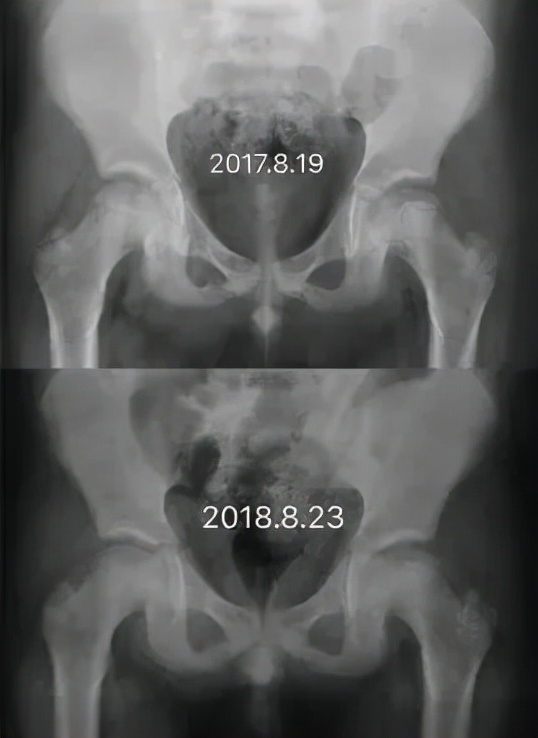

Perthes病即 儿童股骨头特发性缺血性骨软骨病,于1910年被Legg、Calve、和Perthes三位学者总结报道,因此也称为Legg-Calve-Perthes病,简称LCPD。发病早期,患儿往往出现跛行和患侧大腿中下段的疼痛不适、有时甚至是健侧膝盖周围疼痛,休息几天就可以缓解。但由于儿童天性活泼好动,上述症状常常容易复发。因此好多孩子常常被家长乃至初诊医生忽视、只是简单认为是“滑膜炎”、“缺钙”或者所谓“生长痛”,没有早期发现并且及时确诊、科学施治,而遗留了头臼曲率适应不佳、髋臼覆盖不良、股骨近端形态异常等等生长发育畸形(图1),导致髋关节出现软骨磨损继而早发骨性关节炎,从而严重影响日常生活和工作。而如果能够早发现早治疗,LCPD完全可以获得优良结果乃至正常髋关节状态(图2)!

图2 LCPD患者影像学变化